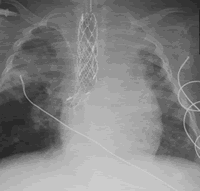

On 29 June 2009 Leah was taken into theatre to do a bronchoscopy and balloon dialation. The bottom part of her trachea collapsed again and she was struggling on the low ventilator settings. It looks like the two bronchi are also narrowed. We are not sure what they want to do, maybe a stent or just time for the trachea to heal and harden?

Dr Colsen took Leah in for the Balloon Dialation on monday 20 July. He said afterwards that the trachea and the two bronchi collapsed down again. The airway is soft and floppy. Best described as a balloon that's inflated and then deflated. My heart skipped a beat as he said that. We were really hoping that the cartilage rings would have formed by now. The plan is to do the stent.

1. CT-Scan (Which shows that the airway and bronchi are open on inspiration but close down on expiration. She will need further intervention ie. the stent);

On the stent: We are still waiting for the company to come back to us on which stent to use for the stenosis that Leah has. Prof Kinsley has been in contact with Dr Elliot from Great Ormond Street Hospital in London and it looks like he might be coming over to do the operation on Leah when necessary.

We have spoken to Prof Kinsley about Leah and the stent. We have decided not to do this operation now. The operation is very difficult and there could be a lot of complications. The stent could either not be removed or it would get stuck to the trachea. The other thing that made us decide not to do the operation now is because she might not make the operation.

For now Leah will be kept stable. The plan is to do another balloon dialatation in 3 months with a size 10 and then in another 3 months time another balloon dialatation with a size 12. The trachea is malacia which means it is very soft and not staying open. Hopefully in time the cartilage will form and get hard so that the trachea can stay open.